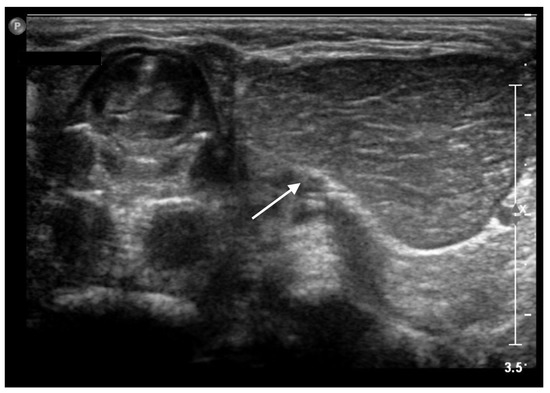

The child was admitted to our Pediatric Unit for further investigation. On clinical examination, the cervical mass appeared painless, tender to the touch, movable in the surrounding tissue. The remainder of the child’s general physical examination was unremarkable. Blood tests were within normal limits in relation to age. An MRI under anesthesia was carried out, showing an oval mass in the left side of the neck, just beneath the submandibular gland, without significant mass effect. The lesion appeared isointense to the thymus gland on all sequences and showed a slight enhancement in the central area, being compatible with ectopic thymus gland. T2-weighted scans showed a well-demarcated quadrilateral-shaped lesion with homogeneous intermediate signal intensity, consistent with ECT in the left latero-cervical region. On Short TI Inversion Recovery (STIR) MRI sequences, the mass appeared isointense to the mediastinal thymus gland (Figure 3).

STIR sequences showing a left cervical mass (white arrow), isointense to the mediastinal thymus gland (white star).